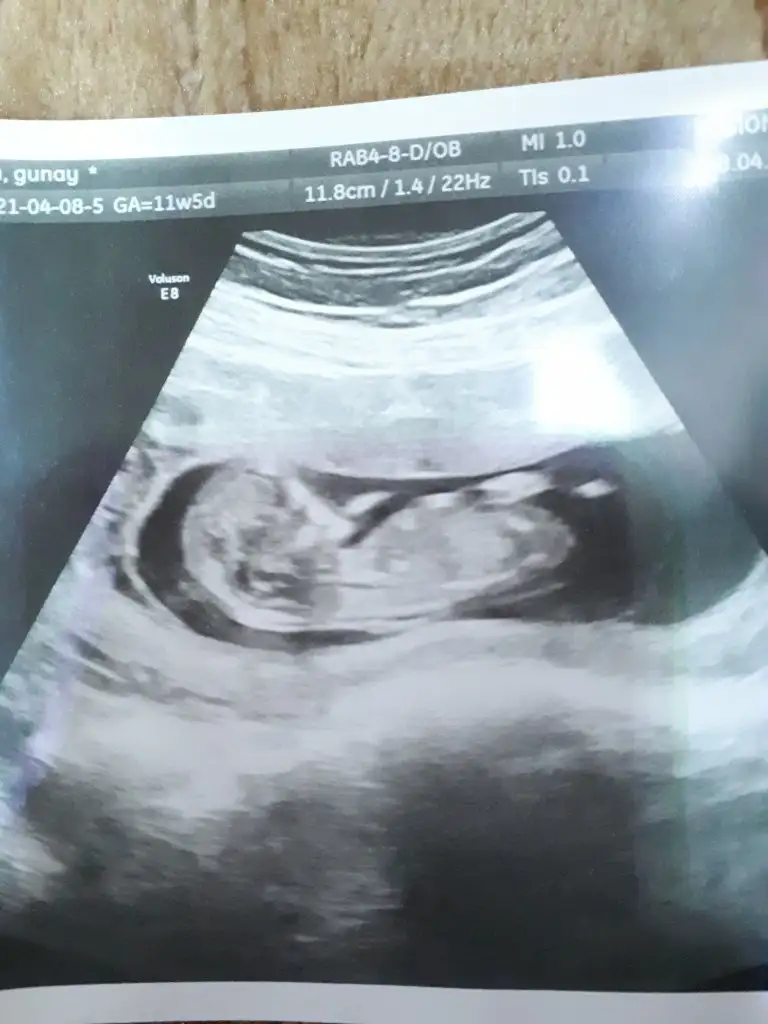

Kız görünüyor13+4 tahminde bulunurmusunuz

Erkek sanki 12 13 haftalar olmaliIkra meyra canım 10+5 ultrason görüntüsü bu.

Merhabaaa bana kız demiştiniz bildiniz kızımız olucak Allah'ın izniyle11+4 de kız demiştim ama 14+5 de artık organı oluşmuş oluyor bakalım hayırlısı olsun tipi kız gibi

Kız sanki bacak arası boş görünüyorCanım 13+4 ne diyorsun? İlk attığım usg ye kız demiştin ikinciye erkek dedin ama ikisinde de emin değilim daha küçük demiştin. Bende bugün doktora gittin 13+4 haftalıkIkra meyra

Erkek gibi dedi. Bende erkek istiyorum. 1 kızım var.Kız sanki bacak arası boş görünüyorusgniz kötü tatlım umarım öyledir Dr tahmin ettimi

Bide bu resmi var daha bu gun cekildi doktor kiza benzetdi ama kesin diyil dediErkek sanki başka USG varsa paylaşın